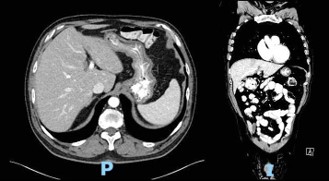

Computed Tomography (CT) scan performed at the time of admission revealed abundant food content with organized appearance in the abdomen (Figure 1), which was morphologically similar to that observed in previous CT scans. The findings supported chronic food retention with difficulty in gastric emptying at the level of pyloric antrum. Pharyngo-esophageal study revealed the presence of a bezoar occupying the entire gastric chamber with normal esophageal motility (Figure 2).

Figure 1: Computed tomography scan at time of admission.